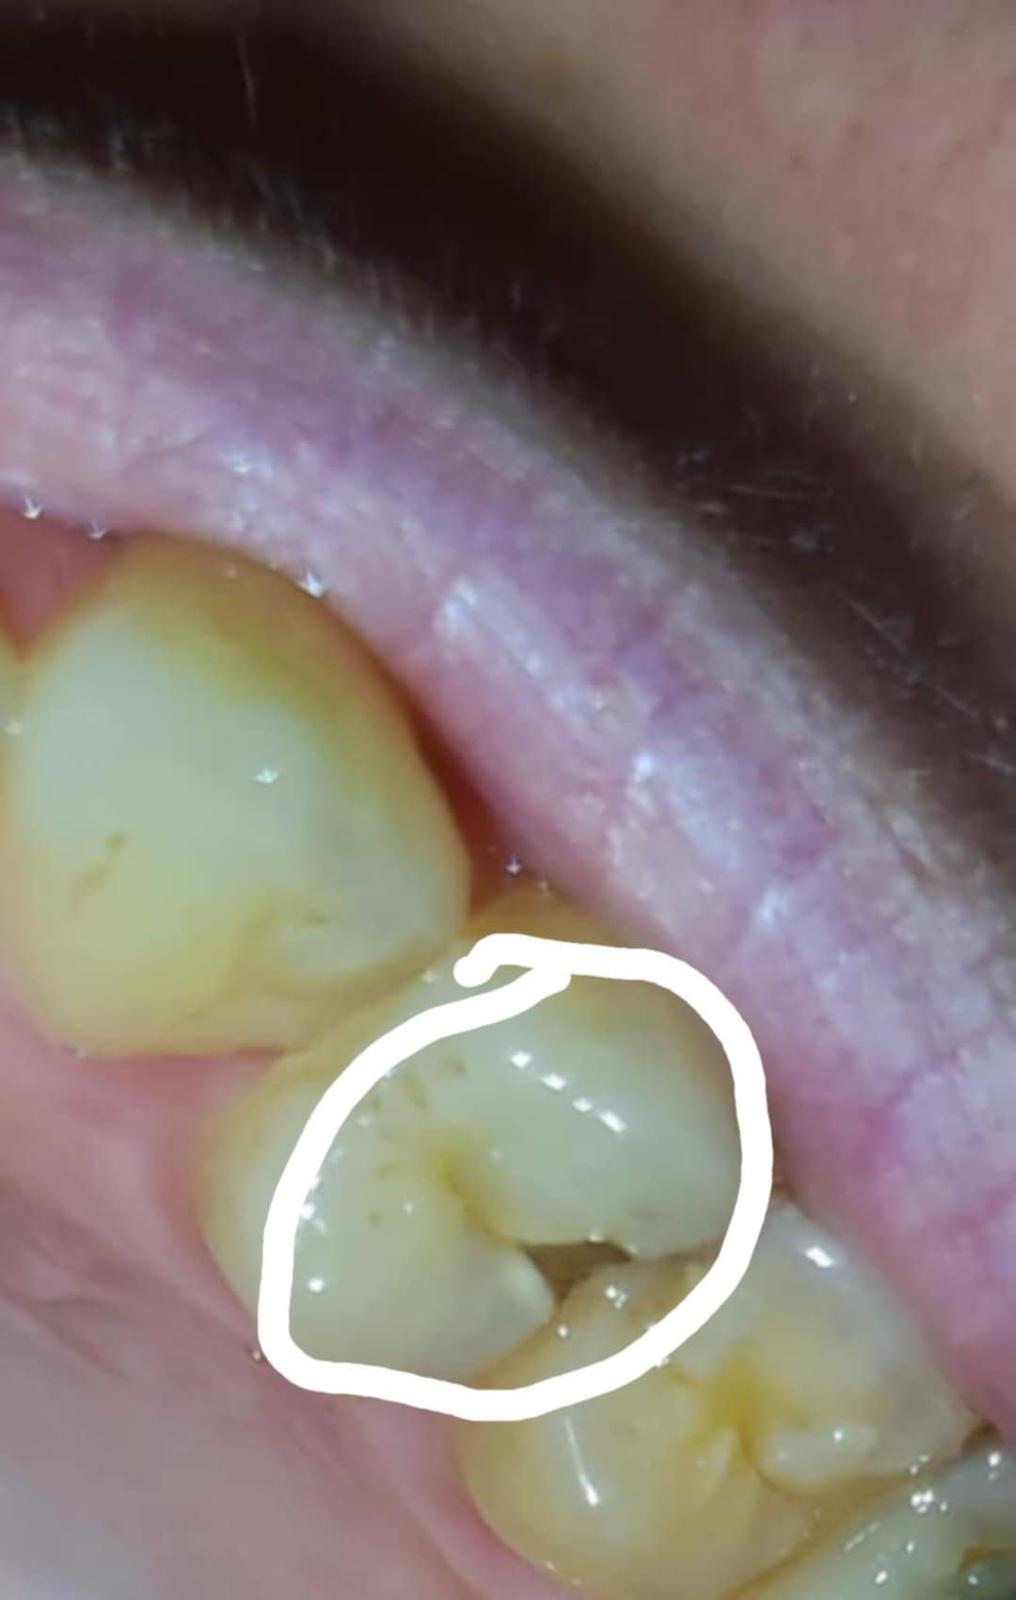

Je to kaz alebo odlomený zub?

Dobrý deň vopred prosím neodsudzujte za stav zubov🙏 je to kaz alebo odlomeny kus zubu ?

Kaz, pokročilá kavitovaná lézia, je vidieť ako je sklovina naokolo demineralizovaná a podmínovaná.

No ale zub sa ti len tak neodlomi a uz duplom na takomto mieste. Je to kaz a vylomeny zub.